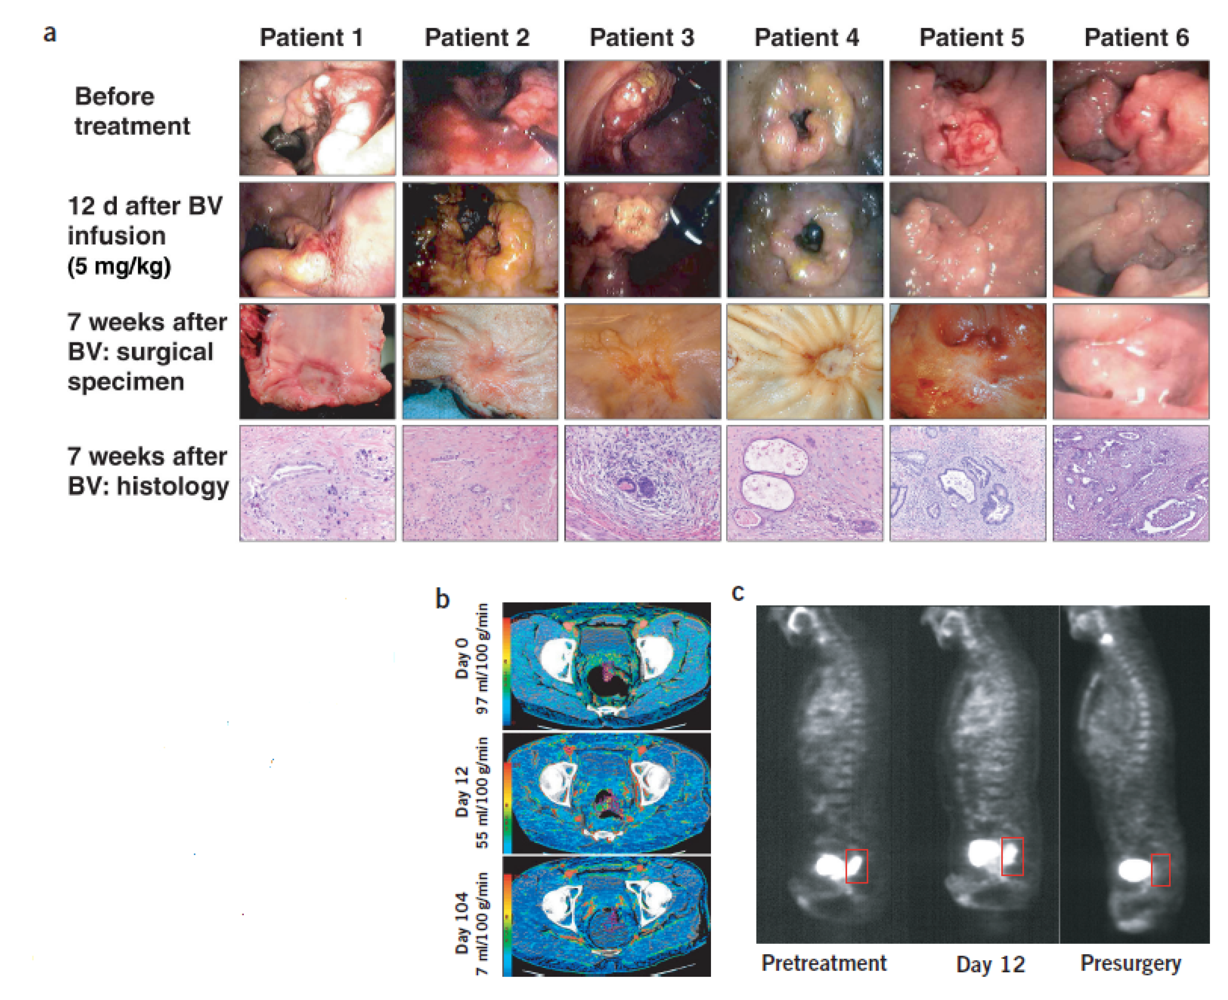

3.3. Can Steady State MRI Monitor Response to Anti-Angiogenic Therapy?

- Ring, J.; Persigehl, T.; Remmele, S.; Heindel, W.; Dahnke, H.; Bremer, C. Monitoring of bevacizumab-induced antiangiogenic treatment effects by “steady state” ultrasmall superparamagnetic iron oxide particles magnetic resonance imaging using robust multiecho DeltaR2* relaxometry. Invest Radiol. 2011, 46, 326–330. [Google Scholar]